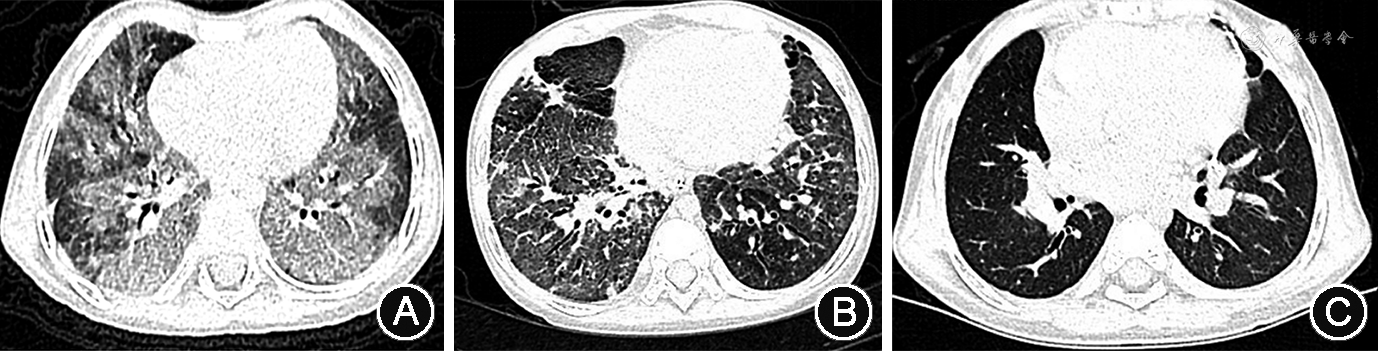

患儿 女,6岁2月龄,因“确诊ABCA3基因变异所致弥漫性肺间质病(diffuse interstitial lung disease,DILD)4年余,接受肺移植6个月,拔除气管套管”于2021年5月在深圳市儿童医院呼吸科病房住院。1岁9月龄患儿因“咳嗽、气促、生长发育落后9个月”于2016年12月在本院就诊,胸部CT提示两肺多发磨玻璃影、透过度不均匀,二代基因测序诊断为ABAC3基因复合杂合变异所致儿童弥漫性肺间质病。确诊初期给予患儿泼尼松、阿奇霉素及羟氯喹三联口服及家庭氧疗(鼻导管1 L/min),间断有咳喘加重或发热,予加强抗感染及抗炎治疗后可缓解。患儿2岁时(2017年3月)复查胸部CT提示患儿双肺弥漫性磨玻璃影进一步加重,双肺透亮度明显降低(图1)。患儿3岁(2018年3月)起因气促、呼吸困难,改为面罩吸氧(4 L/min)。患儿4岁9月龄(2019年12月)因“进行性呼吸困难1年余”再次入住本科,给予经鼻高流量给氧,改为甲泼尼龙每月冲击治疗联合阿奇霉素及羟氯喹口服。患儿5岁(2020年3月)起因“反复出现严重呼吸衰竭,伴有浮肿、腹胀”3次入住本院重症监护病房,胸部CT提示患儿肺部病变明显加重(图1),诊断为“急性肺源性心脏病、重度肺动脉高压、心包积液、腹腔积液、重度营养不良”。患儿5岁6月龄(2020年9月)在外院成功接受双肺移植手术,术后顺利撤出呼吸机,但因出现双侧膈肌麻痹,气管切开中,夜间需接受双水平正压无创通气。患儿系其母第1胎第1产,足月自然出生,出生体重3 150 g,出生情况正常,精神、运动发育正常,体重增长缓慢,5岁6月龄接受肺移植前体重仅11.5 kg。家族中否认类似病史及遗传病史,其父母亲体健,为ABAC3基因变异携带者。

诊疗经过:入院后患儿继续口服环孢素及泼尼松抑制移植后排斥反应,接受支气管镜检查未发现有气道肉芽及明显气道狭窄或软化,胸部CT提示右肺上叶陈旧性实变,无移植后间质性肺损伤改变(图1)。行多导睡眠监测提示低通气及矛盾呼吸,考虑双侧膈肌麻痹所致。遂予堵管、拔除气管切开套管,夜间改为经鼻双水平正压通气,予出院,定期随访复查。